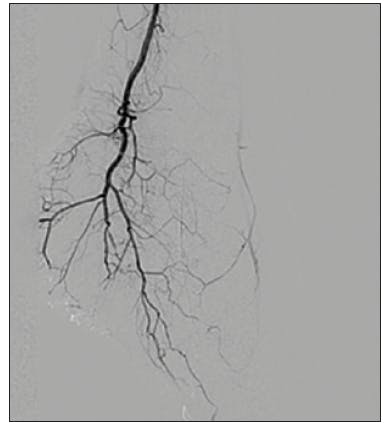

We started with laser atherectomy followed by percutaneous transluminal angioplasty of the tibial peroneal trunk, peroneal artery, and posterior tibial artery. Angiography of the posterior tibial artery revealed embolization to the heel resulting in no flow to the foot (Figure 1). After one pass with mechanical thrombectomy using CAT RX, the thrombus was removed and flow was restored to the pedal arch via the plantar posterior tibial artery (Figure 2 and Figure 3).

DISCUSSION

The Indigo System CAT RX was the preferred choice for mechanical aspiration thrombectomy to remove the distal emboli below the knee in the posterior tibial artery. The large aspiration lumen and highly trackable, low-profile design coupled with the power of the Penumbra ENGINE resulted in the successful removal of the emboli in one pass. The deliverability and continuous aspiration power were essential to achieving restoration of flow supporting a positive patient outcome to help heal this case of CLI.